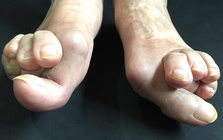

痛みを増し、変形症状、体を支える事が大変になり

歩行の困難、膝や腰などの痛みの発症に。

外反母趾の問題は痛みだけではありません。

その変形症状から多くの身体の不具合と

ほかの症状、病気を発症させてしまう方、